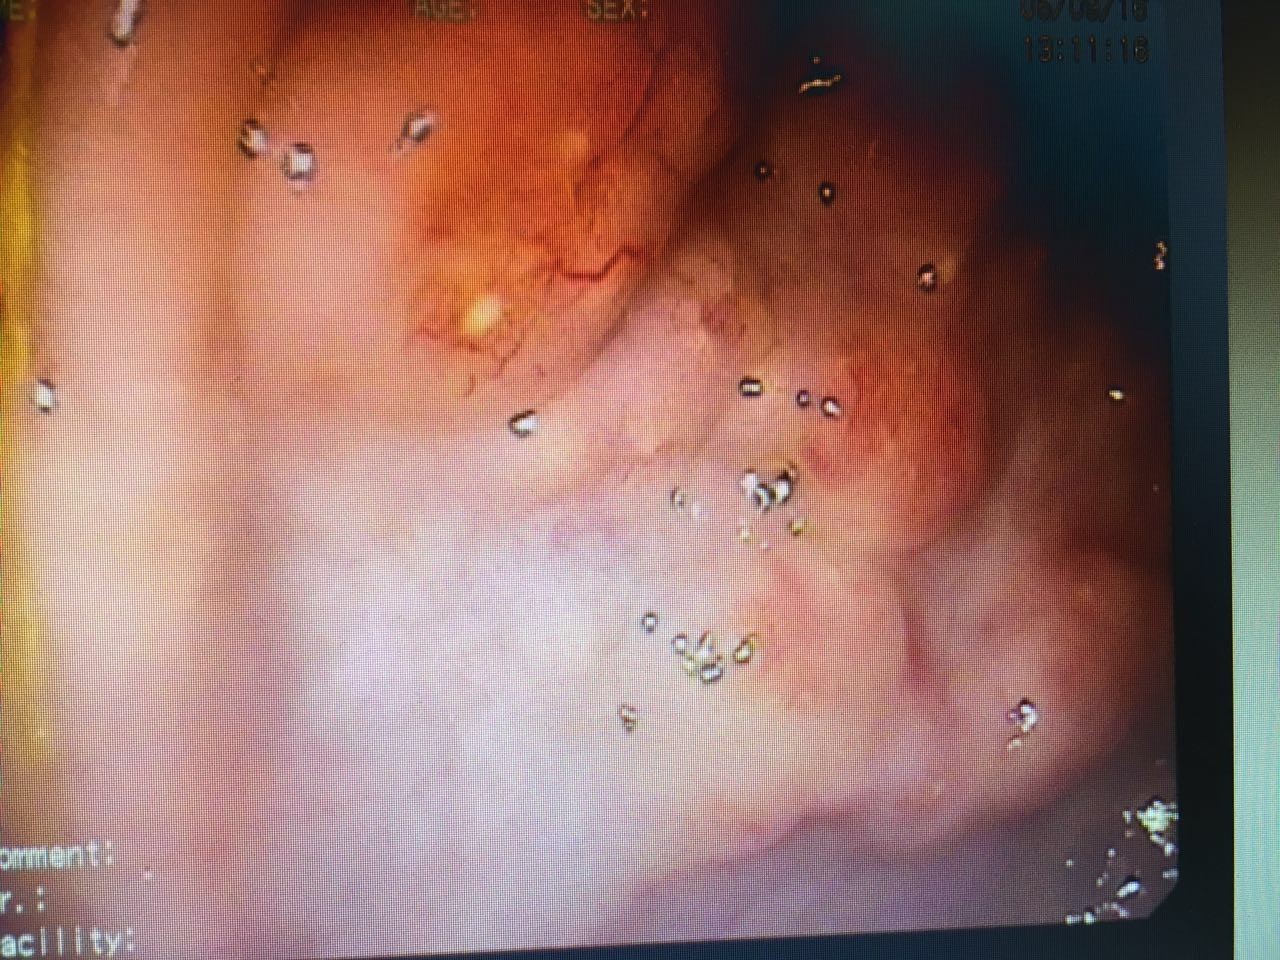

——高热、粘液脓血便、肺部阴影……这是个什么鬼?

抗生素使用后的第三天,热型基本上没有变化,还是午后高热。只不过病人食欲好转了,咳嗽有点减轻,大便次数减少……四环素已经使用了4次,*虫病恙**可以不考虑了;目前结合患者超高的嗜酸细胞,血吸虫血清学反应阳性(大便孵化结果还没有拿到),开始按血吸虫病给予吡喹酮治疗。吡喹酮治疗后24小时,体温最高峰由39度降低到38度,咳嗽消失。从治疗反应来说,比较符合血吸虫感染了,但是患者的体温能够完全降至正常吗?肺部改变一定是血吸虫所致吗?毕竟就已知的血吸虫相关知识而言,血吸虫主要还是寄生在门静脉系统,然后还是在肠系膜下静脉和直肠上静脉产卵……书本有提过血吸虫的肺部改变为间质性改变,因为相对少见而且缺乏具体的表述。毕竟大部分研究血吸虫的文献资料还是在90年代,肺部CT没有普及的时候。根据目前患者的情况,比较可行的确诊手段一个是等大便孵化出尾蚴,还有就是我们消化科先安排肠镜检查看看。结果肠镜做下来,确实有点意思。不仅有我们常见的粘膜表面黄色点状颗粒(聚集成团的血吸虫虫卵)沉着,还有无数个丘疹样隆起(图4),活检了3块。看见这样的表现,我们心里已经基本有数了,回来立刻停了抗生素。在等待病理结果的过程中,患者体温慢慢的降至正常。吡喹酮治疗第六天,患者突然出现肌肉酸痛,一过性皮疹(可惜当时患者不在医院里边,我们没有看见患者也没有拍照),我们考虑为类赫氏反应,给予了激素,次日不适消失。最后肠镜病理回来:见图片5。同时血吸虫防治站的结果也回来了:大便孵化出较多尾蚴。急性血吸虫病得以确诊。

图4